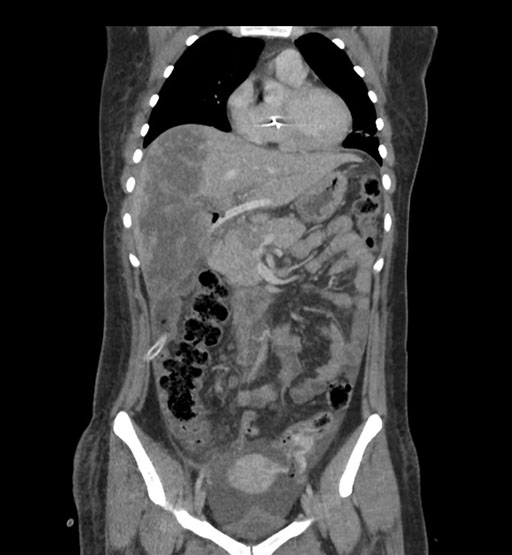

Imaging Analysis

Look through the patient's CT scan to identify any areas of concern for the necessary procedure.

Coronal Venous